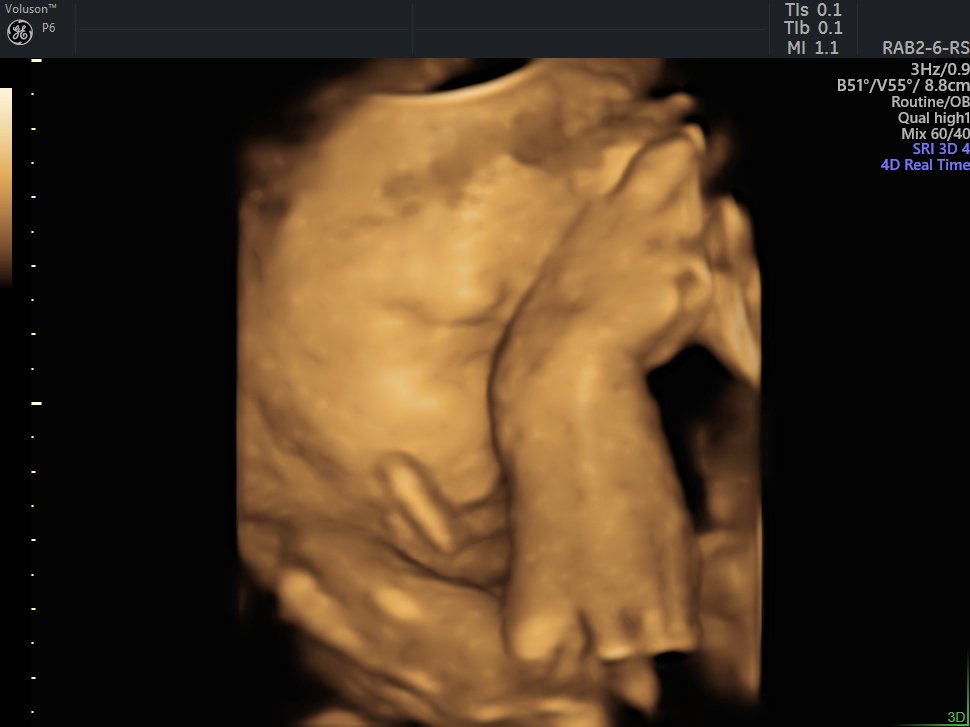

4 D Ultrasonografi

4 Boyutlu (Renkli) Ultrason ve Doppler Ultrasonografi